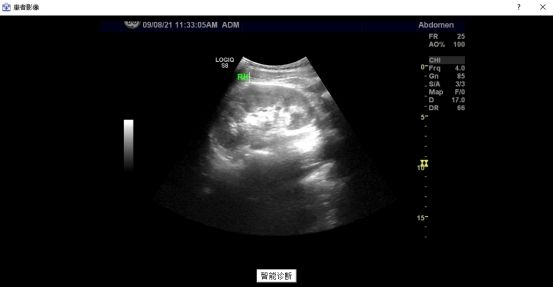

img

并且點(diǎn)擊“智能診斷”按鈕,可以調(diào)用深度學(xué)習(xí)網(wǎng)絡(luò),大致判斷該影像的患者是否患病。